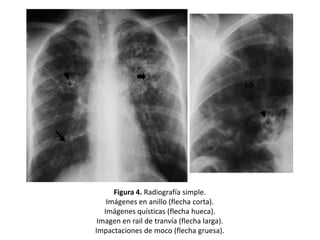

Figura 4. Radiografía simple.

Imágenes en anillo (flecha corta).

Imágenes quísticas (flecha hueca).

Imagen en rail de tranvía (flecha larga).

Impactaciones de moco (flecha gruesa).